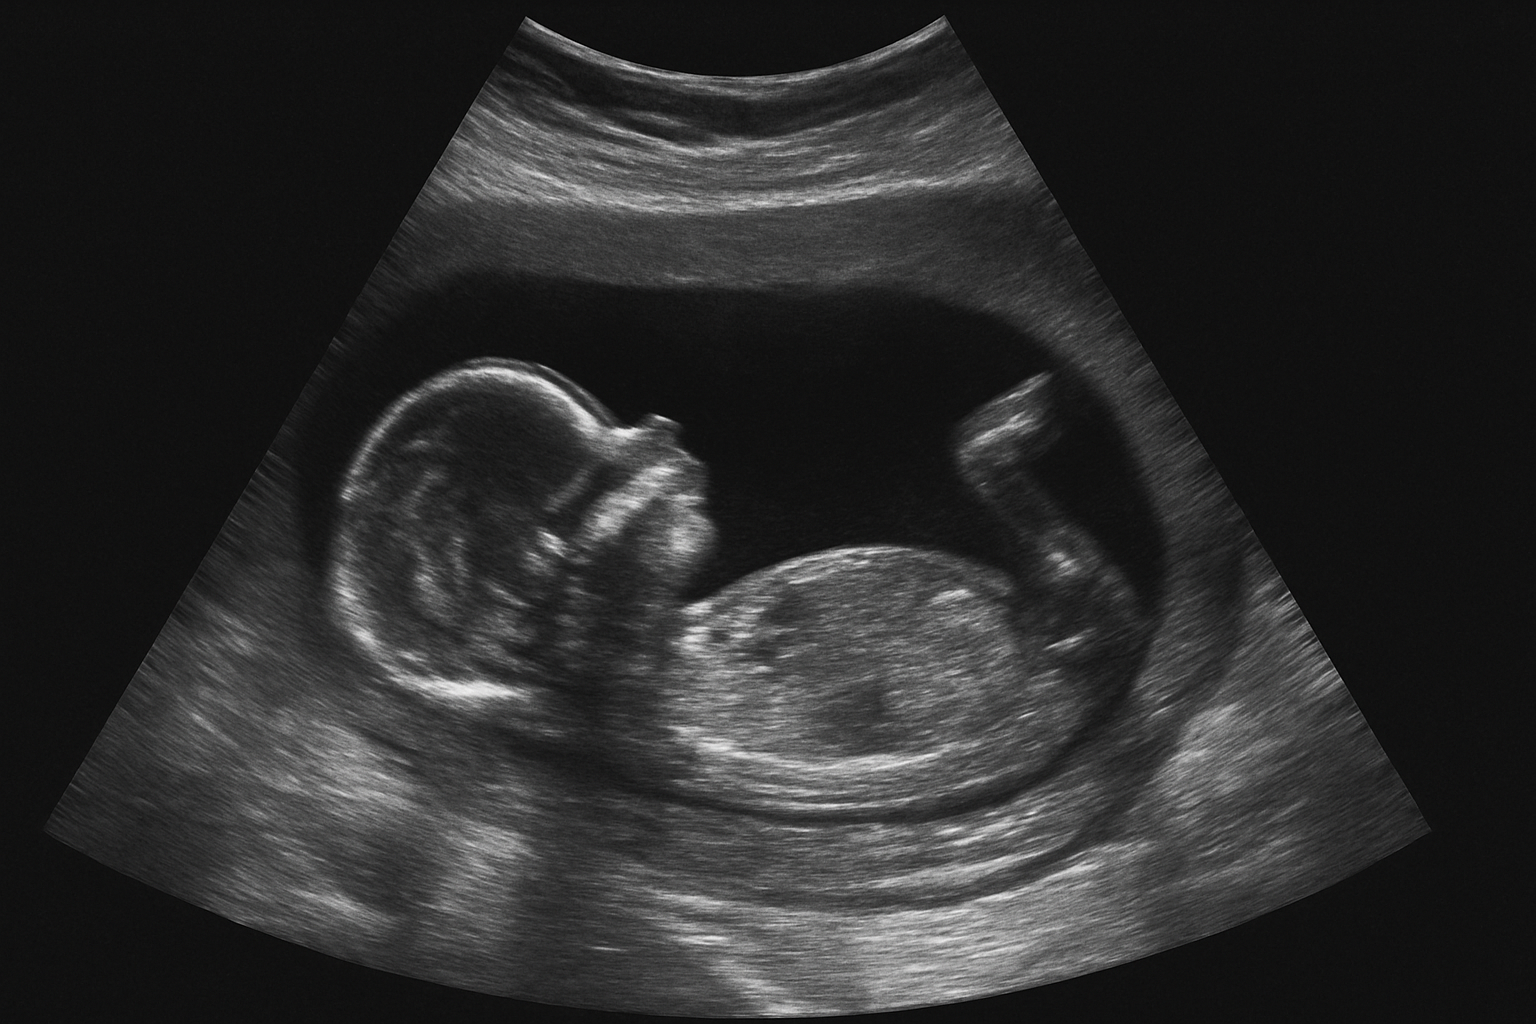

Tussen de 12 en 14 weken kun je een 13-wekenecho laten maken. De echoscopist kijkt dan of er grote lichamelijke afwijkingen zichtbaar zijn, zoals aan het hoofdje of de organen. Deze echo is onderdeel van een landelijke studie en deelname is vrijwillig.

Deze echo krijg je standaard aangeboden, ook als je geen NIPT of 13-wekenecho doet. Er wordt gekeken naar de ontwikkeling van je baby, de ligging van de placenta en eventuele afwijkingen, zoals een open ruggetje of hartafwijking.

Benieuwd hoe je kindje eruitziet op de echo? Bekijk hier foto's van de verschillende